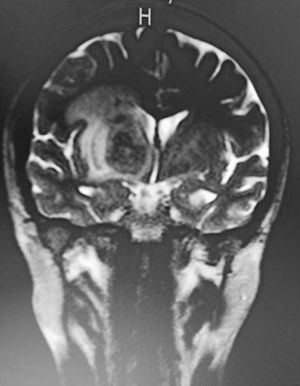

CasoUn paciente masculino de 28 años de edad residente del municipio de Bucaramanga, Santander, cesante, con antecedente de consumo de marihuana, sífilis tratada (24/01/2020) y VIH diagnosticado en 2017 con manejo antirretroviral ambulatorio con mala adherencia al tratamiento entre junio y noviembre del 2020, la última carga viral fue de 44.000 (19/10/2020) sin registro de LTCD4. Ingresó el 26/04/21 refiriendo un mes de temblor en el miembro superior izquierdo, una semana de hemiparesia derecha, fiebre y somnolencia. Se valora al paciente con alerta afebril con hemiparesia e hiperreflexia derecha y temblor en acción de miembro superior izquierdo, sin signos meníngeos, sin signos de hipertensión endocraneana, se toman laboratorios con hemograma sin leucocitosis, sin anemia, sin trombocitopenia con linfopenia, proteína C reactiva levemente positiva, uroanálisis no patológico, azoados normales, electrólitos normales, serología negativa, anticuerpos para hepatitis c negativos, antígeno para hepatitis b negativo, IGM para toxoplasmosis negativo, carga viral 269.301 copias/ml, se toma tomografía axial computarizada de cráneo que muestra una lesión con efecto de masa de predominio derecho en la región ganglio basal izquierda. Se observan lesiones en el anillo hacia la zona central de las lesiones con aspecto edematoso y digitiforme (fig. 1), por lo cual se considera alta probabilidad de toxoplasmosis cerebral, es valorado por neurología, donde contraindican punción lumbar e indican la realización de una resonancia magnética cerebral simple y contrastada bajo sedación, la cual reporta lesiones intra-axiales con edema perilesional localizadas en la región ganglio basal derecha y talámica izquierda, considerando lesiones de tipo inflamatorio (neurotoxoplasmosis). Se da esquema de manejo con fluconazol y trimetropin/sulfametoxazol por 21 días, con mejoría clínica progresiva, por lo que se da el egreso con indicación de continuar la terapia antirretroviral y se agenda una cita de control por neurología para determinar conductas adicionales.

Para su diagnóstico, se debe realizar un enfoque tanto serológico como imagenológico1, siendo la neuroimagen el método que más nos acerque al diagnóstico, en la tomografía computarizada se evidencia el «signo diana» que evidencia lesiones de masa de baja densidad con realce de contraste y circundante edema; sin embargo, el grado de realce del anillo es dependiente del recuento de células T CD4+; ya que a medida que aumenta el recuento de células T CD4+, el realce se vuelve más prominente, por lo tanto, en aquellos que están inmunodeprimidos más gravemente, las características de la tomografía computada de la toxoplasmosis cerebral pueden ser muy inespecíficas, dado que se presenta simplemente como múltiples lesiones parenquimatosas hipoatenuantes con edema circundante. La resonancia magnética es más sensible para detectar dichas lesiones, permite una diferenciación más precisa de otras infecciones o etiologías inflamatorias, y puede definir mejor la cronicidad del absceso, en las imágenes con contraste, en la resonancia magnética la imagen correlativa del «signo diana» de la toxoplasmosis cerebral se define como un «signo de objetivo excéntrico», que, cuando está presente, puede ser revelador, pero es visto en menos del 30% de los casos.